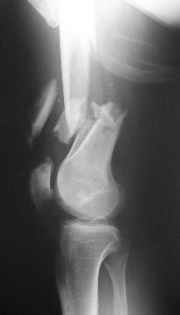

Perfect for retrograde nail + lag screw with this large a distal fragment and this much meta-diaphyseal comminution and this degree of soft tissue injury.

after treatment of open fracture

MUCH less muscle dissection laterally and at the very comminuted distal diaphysis, equal to better fixation with less blood loss, probably better early motion and earlier weight bearing. IF you do have a problem it will be easier to handle than if LISS or other plate fails.